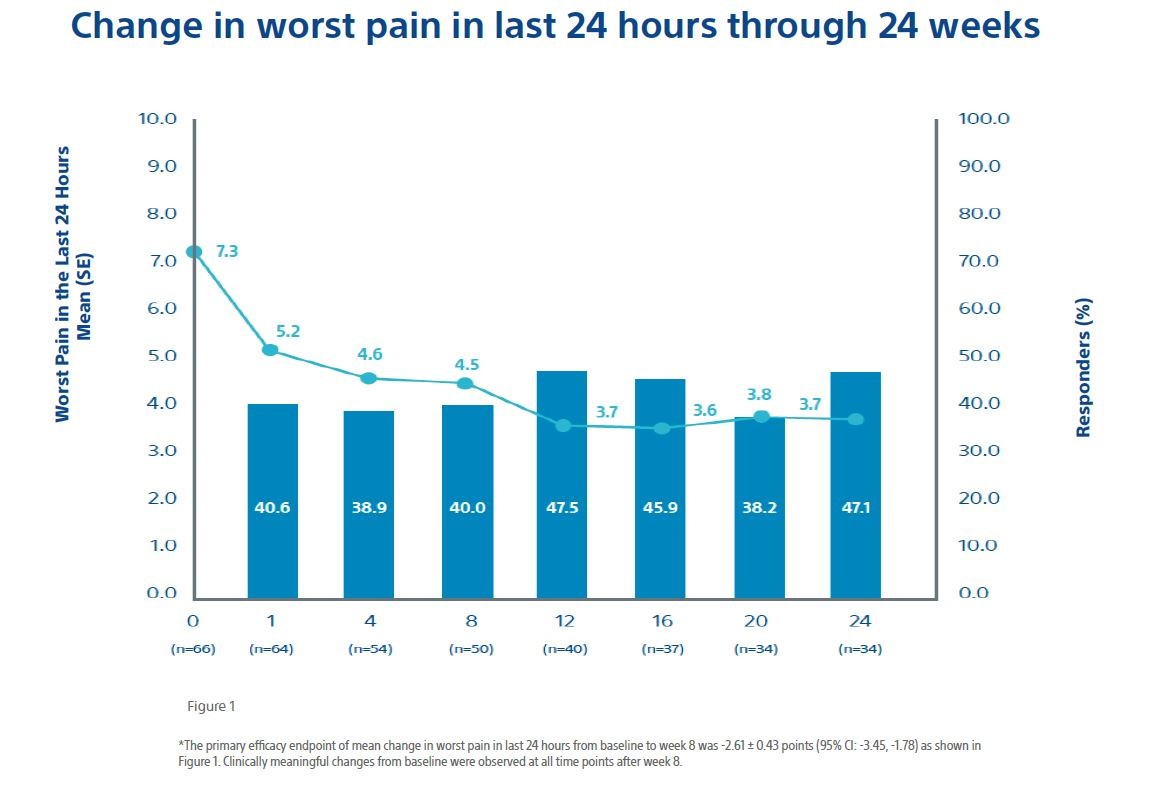

To assess the effectiveness and safety of cryoablation for palliation of painful bone metastases in participants who were not candidates for traditional pain therapies or for whom traditional pain therapies had failed to provide adequate relief. The primary objective was to evaluate the efficacy of cryoablation for pain palliation of bone metastases from baseline to 8 weeks after cryoablation in worst pain in the last 24 hours as measured by the BPI-SF scale.

Separate evaluations of ancillary efficacy endpoints were also made through 24 weeks, including: (a) changes in worst pain scores and average pain scores from baseline; (b) change in analgesic use (both morphine equivalent daily dose (MEDD) and nonsteroidal anti-inflammatory drugs); (c) use of additional therapies for persistent or recurrent pain associated with the index tumor or new metastases; (d) quality of life (as indicated by change from baseline in overall average BPI-SF); and (e) change in Karnofsky performance status as a measure of functional impairment. The safety endpoint was the incidence and severity of procedure or device-related adverse events.

- Primary efficacy objective: change from baseline to 8 weeks after cryoablation in worst pain in the last 24 hours as measuredby the BPI-SF scale;

The primary effectiveness endpoint was the change from pretreatment baseline rating of worst pain in the last 24 hours to post treatment week 8 rating. A clinically meaningful change for this item was defined as a reduction of at least 2 points.

- The Mean pain scores improved by 2 points at 1 weeks and reached meaningful clinically relevant levels after 8 weeks and scores continued to improve throughout follow-up;

- 92% (59/64) of patients achieved pain palliation;

Overall, the data shows a rapid and durable pain relief along with a decrease in MEDD and a corresponding increase in the quality of life for patients with bone metastases.

Most participants achieved their maximum palliation by

| week 1 33.9% 20 of 59 |

week 4 25.4% 15 of 59 |

week 12 15.3% 9 of 59 |